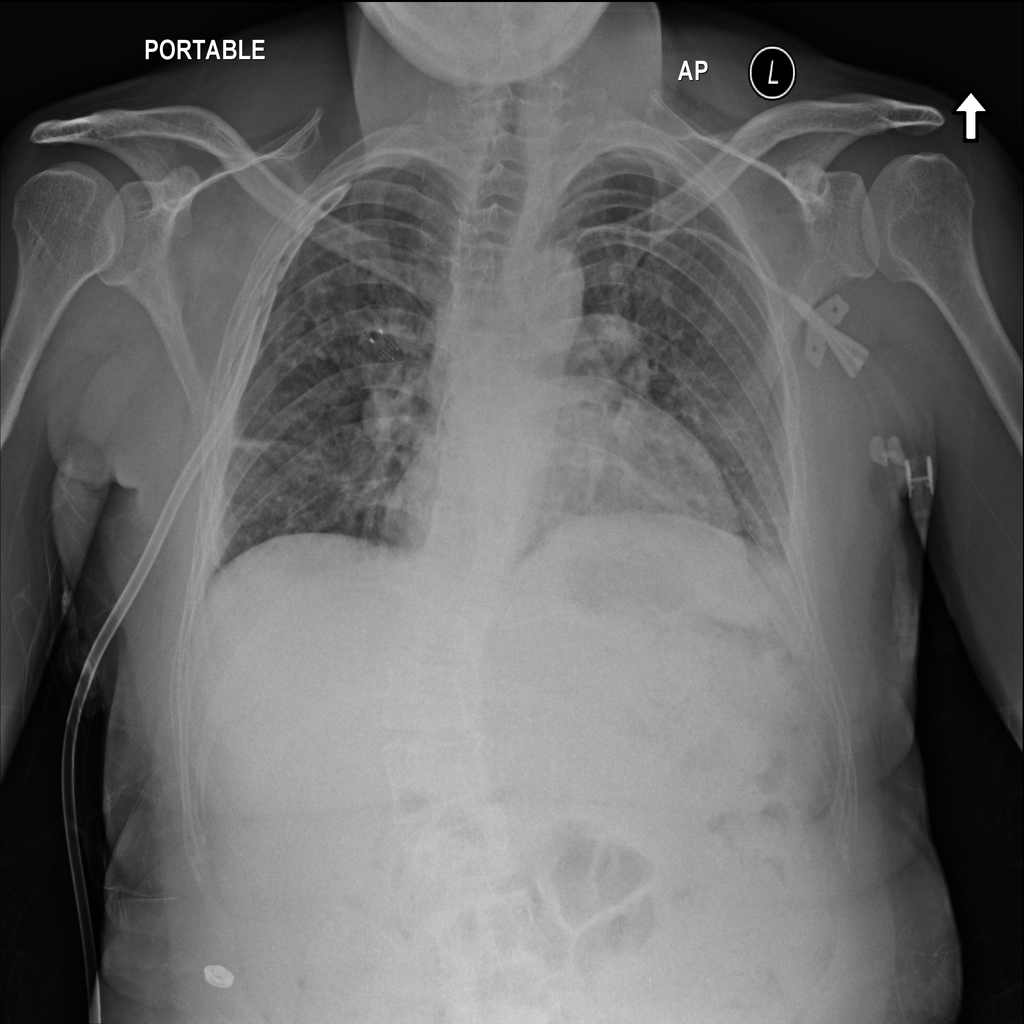

PAT-3384 · IMG-054Atelectasis

PAT-3384 · IMG-054

AP